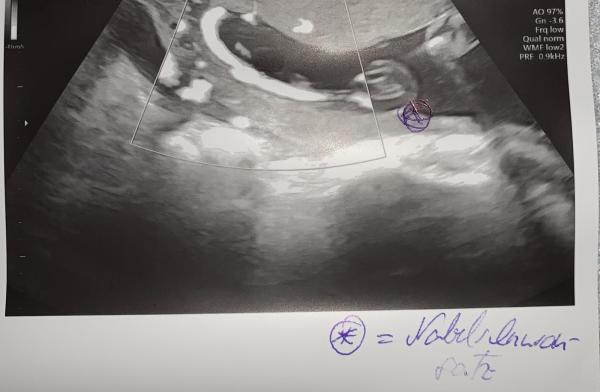

Hallo zusammen, gibt es jemanden bei dem eine Insertio Valementosa (Nabelschnur verwachsen mit der Eihaut) diagnostiziert bekommen hat? Wenn ja was sind eure Erfahrungen? Wer hat natürlich entbunden? Wer hat deswegen einen Kaiserschnitt bekommen?  Ich habe diese Woche erst die Diagnose erhalten und bin nun verunsichert wie es weitergeht. Beste Grüße  23. SSW

Hallo 🙋🏼‍♀️ ich hatte auch die Diagnose in der 20.SSW (September 2022) bekommen gehabt. Ich war dann auch zusätzlich noch in einer Uniklinik zur Bestätigung und der Professor meinte ich könnte auch normal gebären. Als ich aber in der Geburtsklinik in meiner Nähe zur Anmeldung war (November 2022) hieß es von den Oberärzten dort das es ihnen zu riskant sei und hatte einen Termin für einen geplanten Kaiserschnitt 2 Wochen vor ET ( 18.02.2023) bekommen gehabt (geplant war der KS am 02.02.2023) Leider hatte unsere Tochter beschlossen gehabt 5 Wochen vor ET (13.01.2023) auf die Welt kommen zu wollen, in dem Fall war es wegen Vorzeiten Wehenbrginn ein Notkaiserschnitt. Für uns war klar, das wir uns die Plazenta anschauen wollten nach der Geburt, was wir auch gemacht haben, laut den Ärzten und Hebammen die sie mit uns angeschaut hatte, stand definitiv fest, dass unsere Tochter eine normale Geburt auf keinen Fall überlebt hätte, da die Insertio verlamentosa doch zu stark ausgeprägt war. Also für mich war es so genau richtig mit einem Kaiserschnitt und würde mich jederzeit wieder dafür ebtscheiden

Der nabelschnuransatz war vorne links

Bild zu